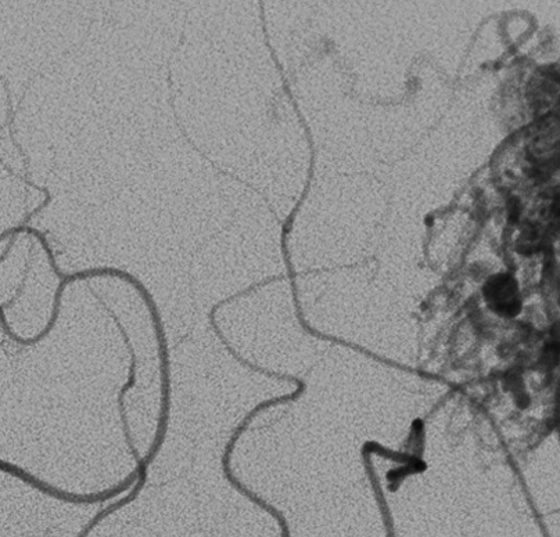

• Okklusionstherapie intrakranieller Aneurysmen

Endovaskuläre und neurochirurgische ­Möglichkeiten

Eine aneurysmatische Subarachnoidalblutung (aSAB) ist mit hoher Mortalität und Morbidität vergesellschaftet. Nach initialer Stabilisierung des Patienten muss durch neurochirurgische und/oder endovaskuläre Therapieformen die Blutungsquelle ausgeschaltet werden. Aneurysmen, die für beide...…